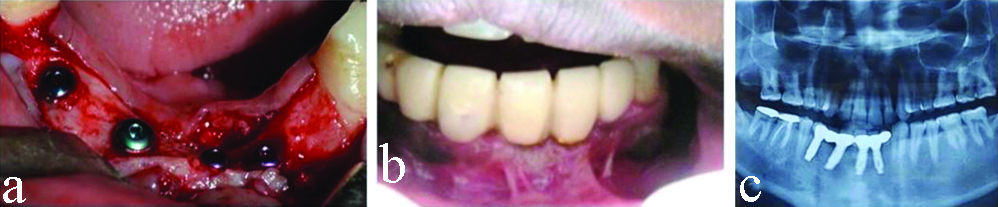

Five months following ridge augmentation, a second surgery was performed for implant placement in grafted site. Site re-entry was done following incision line of first surgery. Fixation screws were removed after assessing block stability. Four implants (Osstem Implant System; two of 11.5×3.5 mm, one each of 11.5×4.0 mm and 11.5×4.5 mm) were placed in planned positions using manufacturer specified drilling protocol [Table/Fig-3]. The planned positions of the four dental implants in the mandible were: left central incisor region, right lateral incisor region, right canine region and right first premolar region. All drills and implant measurement equipment used were of Osstem Implant System. All drillings were performed at insertion torque between 25-35N. Initially, a punch cut was made using pilot drill at 1,500 rpm to determine the fixture position. This was followed by use of 2.0 mm diameter twist drill at a speed to 1,500 rpm which was extended till the desired length of the planned implant (right central and lateral incisor, canine and first premolar regions). Achieved depth was confirmed using a depth gauge. Subsequently, larger diameter drills were used at speeds of 800 rpm to 1,200 rpm till the desired diameter was achieved. All drillings were done under copious irrigation. Orientation of two adjacent implant holes was confirmed using parallel pins before proceeding with implant insertion. Provisional prosthesis was given three months after implant placement to improve patient’s aesthetics [Table/Fig-3]. Postsurgically the patient was asked not to consume hard and hot food, not to use straw for consuming liquid, to avoid forceful spitting by creating negative suction pressure, not to evert the lip to see the surgical site in the mirror, not to poke the surgical area with tongue or any other aid such as toothpick and not to brush in the area. Patient was asked to do ice pack application in the area and switch to warm saline rinses after 24 hours.

a) Dental implants in place; b) Temporary prosthesis in place with high frenal attachment (gingival attachment) and low vestibular depth, c) Orthopantogram showing dental implants in place.